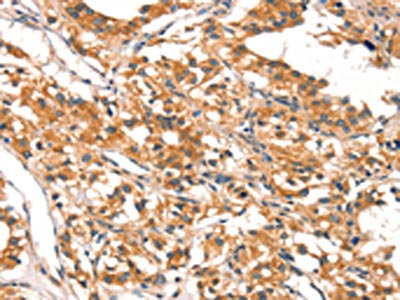

The image on the left is immunohistochemistry of paraffin-embedded Human thyroid cancer tissue using CSB-PA167820(DAB2IP Antibody) at dilution 1/20, on the right is treated with synthetic peptide. (Original magnification: ×200)

The image on the left is immunohistochemistry of paraffin-embedded Human gastric cancer tissue using CSB-PA167820(DAB2IP Antibody) at dilution 1/20, on the right is treated with synthetic peptide. (Original magnification: ×200)